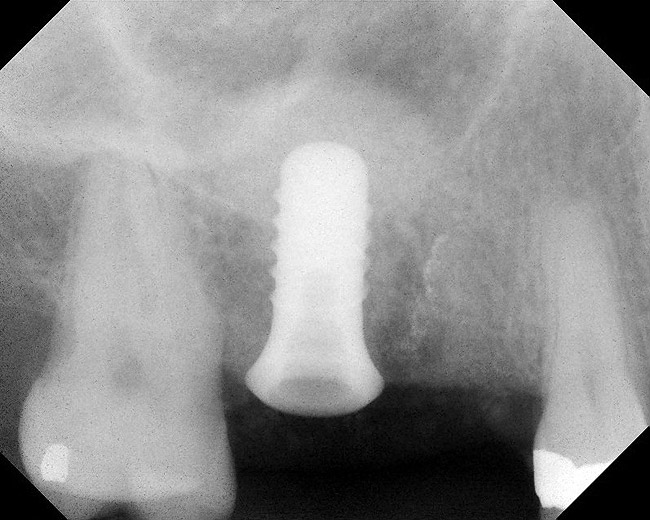

Figure 8  Radiographic confirmation of implant osteointegration into the new bone 14 months after the initial surgery.

Figure 8